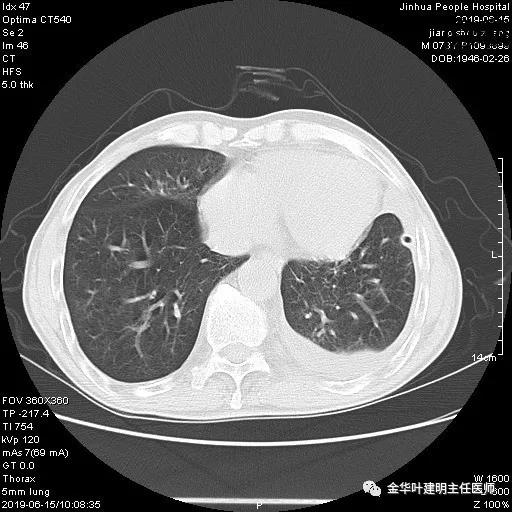

以上是肺窗表现,下面为纵隔窗影像:

因为引流出的胸液为血性,但感觉不是特别鲜,查血色素9.5 g/L,术前是12.7g/L。当时考虑胸腔内出血可能,较为纠结的是是否需要进胸探查。但鉴于血压正常、心率不快,一般情况良好,不似胸内大出血休克的表现,所以仍想继续观察保守治疗。